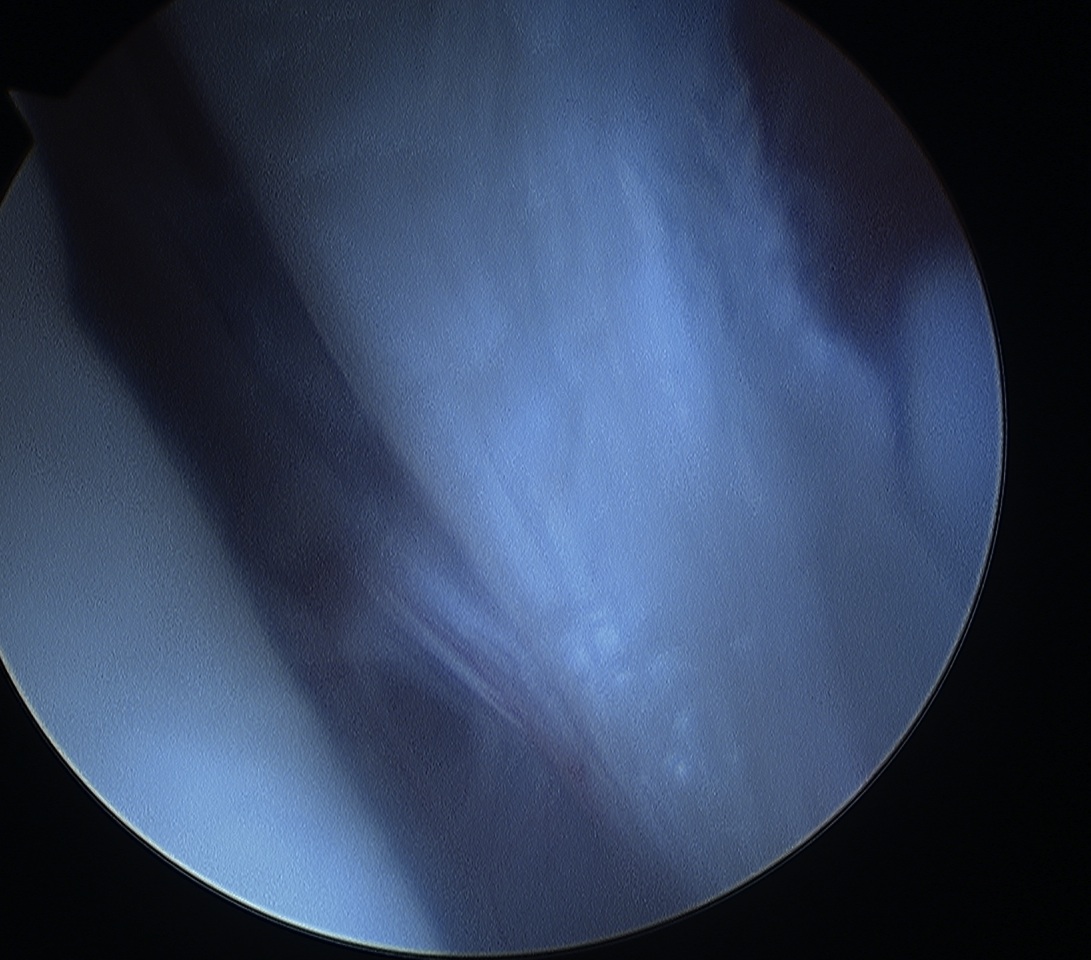

Debride anterior glenoid bone to bleeding bone

Shoulder Arthroscopy Bony Bankart